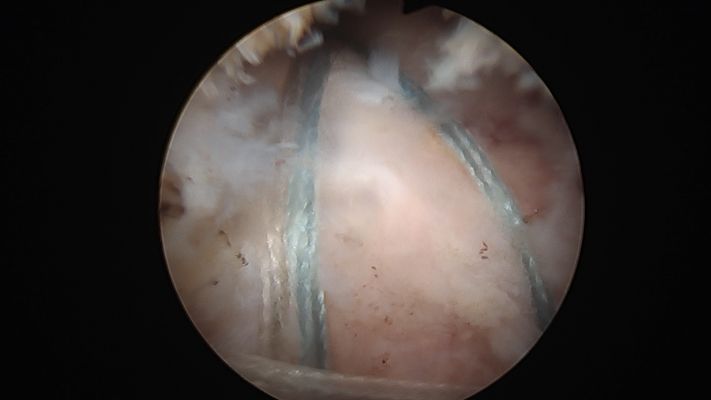

La artroscopia se realiza mediante pequeñas incisiones de aproximadamente 0,5 a 1 cm, con la ayuda de una cámara podemos ver el interior del hombro e identificar la rotura del tendón y se repara utilizando unos tornillos o anclajes cargados con hilos muy fuertes para fijar el tendón en el lugar correcto.

Rotura del supraespinoso. Visión por artroscopia.